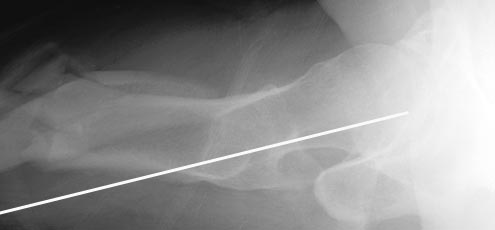

АЖ> Дык и я о том же! Не о репозиции перелома, а о введении штифта в

При многооскольчатых переломах стержень может "выпасть" кзади под весом кондуктора и своим, даже если поначалу он вводился правильно. Чтобы эту неприятность предупредить, стоит ввести спицу по оси шейки бедра вдоль ее задней стенки, типа как на картинке. Если стержень кпереди от этой спицы вводить, то он за нее не провалится.